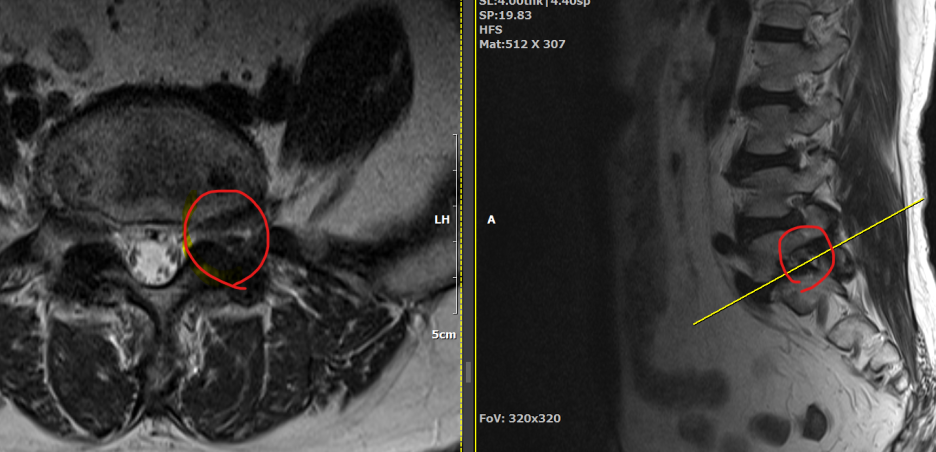

척추관 협착증은 척추관이 좁아지거나 협착되어 척수나 신경근을 압박하는 상태를 말합니다. 이런 경우, 양방향 척추 내시경이 매우 유용한 치료 수단이 될 수 있습니다.

- 계획: 양방향 척추 내시경은 미세한 카메라와 도구를 사용하여 척수와 주변 신경 구조를 정밀하게 시각화할 수 있습니다. 이를 통해 정확한 진단을 내릴 수 있으며, 각 환자에게 맞는 개별적인 수술 계획을 수립할 수 있습니다.